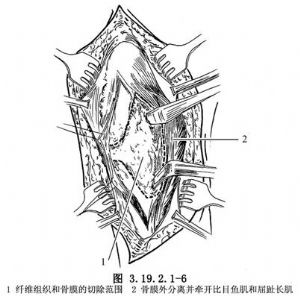

切開皮下和深筋膜,向前後遊離皮瓣,保護大隱靜脈和隱神經,顯露假關節和病變組織(圖3.19.2.1-5)。骨膜外仔細分離並向後牽開比目魚肌和趾長屈肌,以顯露後側的病變組織。徹底切除包圍假關節的增厚纖維組織和骨膜(圖3.19.2.1-6)。